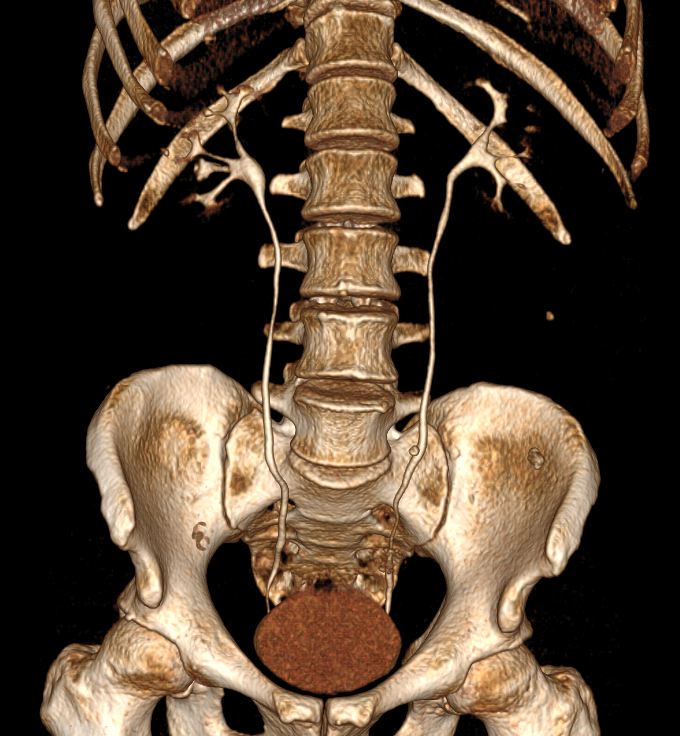

Данный формат позволяет проводить угловые и линейные измерения, изменять яркость, контрастность. Исходные данные, полученные при томографии, используются:

- для реформатирования изображений в различных плоскостях;

- трехмерных реконструкций.